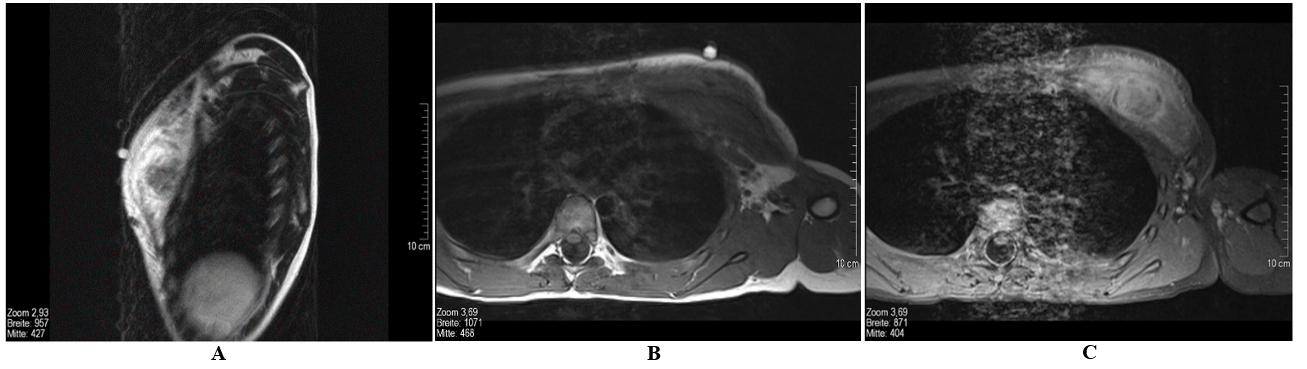

The parents were told to wait and see how the lesion develops and return for further consultation in case of persistence or progression of either the swelling or the symptoms. Physical examination two weeks later showed a progression in size leading to MR imaging of the boy’s thorax. MRI revealed a round, intrapectoral mass of about 2.6 cm in size with marked perifocal edema and inhomogeneous enhancement of contrast media (Figures 2 & 3). Since this morphologic description rather matched a tumorous mass than either an inflammatory lesion or haematoma, incisional biopsy was recommended. The patient undergone this procedure two days later. The histological work-up presented the diagnosis of nodular fasciitis of the major pectoralis muscle. The complete resection with preservation of the muscle was performed one week later. The young patient presented to clinical and sonographic follow-up two months after the operation without symptoms or recurrent disease.

Figure 2: Magnetic resonance tomography of the thorax, without contrast media. A) Coronal STIR, B) coronal True-FISP-Sequence: marked edema of the left major pectoralis muscle. Intramuscular mass, approx. 2.6 cm diameter, which is partly isointense and partly hyperintense compared to the surrounding muscles.

Figure 3: Magnetic resonance tomography of the thorax. A) Sagittal T1 SE (with marking), B) transversal T1 TSE, C) transversal T1 fs after administration of contrast media. Extensive, space-occupying edema of the left major pectoralis muscle. Intramuscular mass, approx. 2.6 cm diameter, which appears partly isointense and partly hyperintense compared to the surrounding muscles in the STIR sequences and isointense in the T1w sequences. Inhomogeneous enhancement of the mass and reactive absorption of contrast media by the edema is seen after administration of contrast media.

There is only a little literature on intramuscular nodular fasciitis, such as in our case. The few existing reports state that this variant accounts for up to 10% of all findings in nodular fasciitis [1]. Not much is known on the pathogenesis of the disease. Assumptions have been made that there is an association to trauma (as in our case) [39]. The lesions can be detected easily in imaging. With ultrasound, they appear as well as distinguishable, mixed hyperechoic and hypoechoic lumps or masses (Figure 1) with slightly increased perfusion of the deep subcutaneous tissue adjacent to the fascia [39]. MRI cannot distinguish the various subtypes of nodular fasciitis such as myxoid, cellular or fibrous. Unfortunately, the morphology is very heterogenic and can mislead to the diagnosis of soft tissue sarcoma [40, 41]. When viewed in T1w sequences, lesions which are rich in cells are nearly isointense compared to musculature and hyperintense compared to fatty tissue in T2w sequences. Fibrous lesions however are hypointense in all sequences. Usually, the enhancement of contrast media is diffuse but can sometimes be located only peripherally (Figures 2 & 3) [42]. Biopsy is needed to confirm diagnosis in nearly every case. Genomic rearrangements of the USP6 locus are found in 92% (44 of 48) of nodular fasciitis [43]. Tomassen et al. recommended molecular analysis of untypical cases to avoid overtreatment due to misdiagnosis, which was previously described [3, 37].